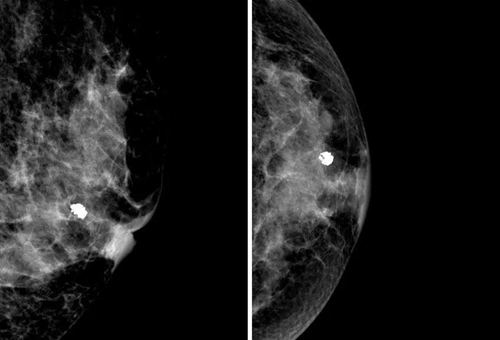

乳房的鈣化點大部分都是良性的,或伴有其他良性病變,如乳腺增生。所以,乳房鉬靶上如果看到大大的白點,通常就是良性鈣化點,如纖維腺瘤就常常會在鉬靶的影像上出現(xiàn)爆米花狀的粗糙大白點。

2. 女性乳房里常常有纖維腺瘤,腺瘤里的腺體也會聚積鈣鹽,在影像上呈現(xiàn)出粗大的白點;